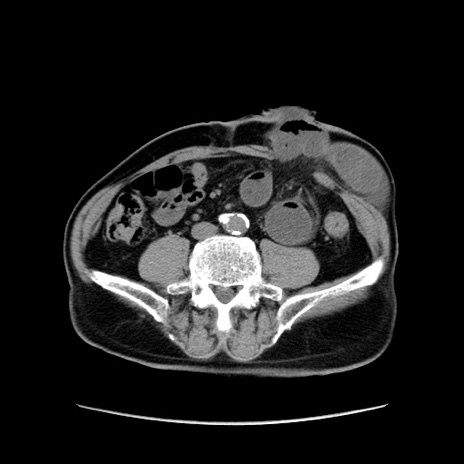

症例24(横断像)

【症例】80歳代男性

【主訴】左側腹部痛、嘔吐

【現病歴】本日早朝より左腹部に痛みあり。昼頃嘔吐認めたため、救急要請。

【既往歴】直腸癌(Mile手術)、胆摘

【身体所見】意識清明、BT 35.9℃、BP 221/93mmHg、SpO2 97%(RA) 、腹部:左ストーマ周囲に限局性の腹部膨隆あり。 膨隆部自発痛・圧痛あり・軟。

【データ】WBC 7700、CRP 0.09